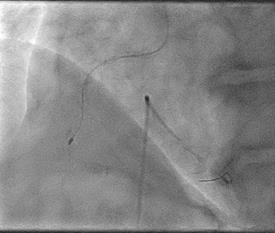

Can thiệp ngã ba động mạch liên thất trước và nhánh chéo 1 với hai stent có bọc thuốc bằng kĩ thuật cullote. Tiếp tục can thiệp động mạch vành phải với ống thông can thiệp (guiding catheter) (Cordis JR4 cm 6Fr) và dây dẫn (Asahi Sion 0.014”). Nong tổn thương bằng bóng 3.5 x 15mm (Neich Sapphire), bóng 4.0 x 12 (NC Quantum Apex), bóng cắt 3.5 x 15 (Cutting balloon, Angiosculpt) không làm vỡ được mảng vữa xơ. Quyết định dùng hệ thống khoan cắt mảng vữa xơ với dây dẫn mềm (Boston Scientific Rotablator Rotalink Plus) và mũi khoan (burr) 1.5mm. Tuy nhiên vì kích thước động mạch quá lớn nên mũi khoan đi qua tổn thương mà không chạm vào mảng vữa xơ được. Chuyển sang mũi khoan có đường kính lớn hơn 2.15mm với tốc độ khoan 150000 vòng /phút. Khi mũi khoa đi qua được 1/3 tổn thương thì không thể di chuyển được tiếp. Nhận định tại thời điểm đó là mũi khoan bị kẹt trong tổn thương tại đoạn giữa của động mạch vành phải. Ngay lập tức các bác sỹ có kinh nghiệm can thiệp trong bệnh viện được mời đến phòng can thiệp đồng thời thông báo cho các phẫu thuật viên tim mạch chuẩn bị trong trường hợp cần thiết. Bệnh nhân có biểu hiện đau tức ngực trái, tuy nhiên mạch và huyết áp tương đối ổn định, điện tim không thay đổi. Dòng chảy trong động mạch vành còn duy trì nhưng chậm TIMI 2. Sau khi hội ý, hướng xử trí đầu tiên là dùng dây dẫn cứng Conquest Pro (Asahi) để đi qua tổn thương nhưng không thành công. Sau đó chúng tôi quyết định cắt đoạn đầu của hệ thống nối mũi khoan, đưa ống thông heartrail (Terumo) sát vào mũi khoan nhằm thay đổi tư thế và cố định mũi khoan vào dây dẫn để đưa ra ngoài. Cuối cùng mũi khoan được đưa ra ngoài thành công. Tổn thương tiếp tục được nong bằng bóng cắt và bóng áp lực cao và đặt được giá đỡ kim loại (stent) bọc thuốc 4.0 x 26mm. Kết quả là động mạch vành được mở rộng hoàn toàn, bệnh nhân không còn đau ngực, huyết động ổn định.

Hình 1: A- hình ảnh động mạch vành trước can thiệp; B – dùng bóng cắt (cutting balloon) không phá vỡ được cấu trúc mảng vữa xơ; C – mũi khoan 1.5 không chạm vào được mảng vữa xơ vôi hóa; D – mũi khoan 2.15 bị tắc tại vị trí hẹp.